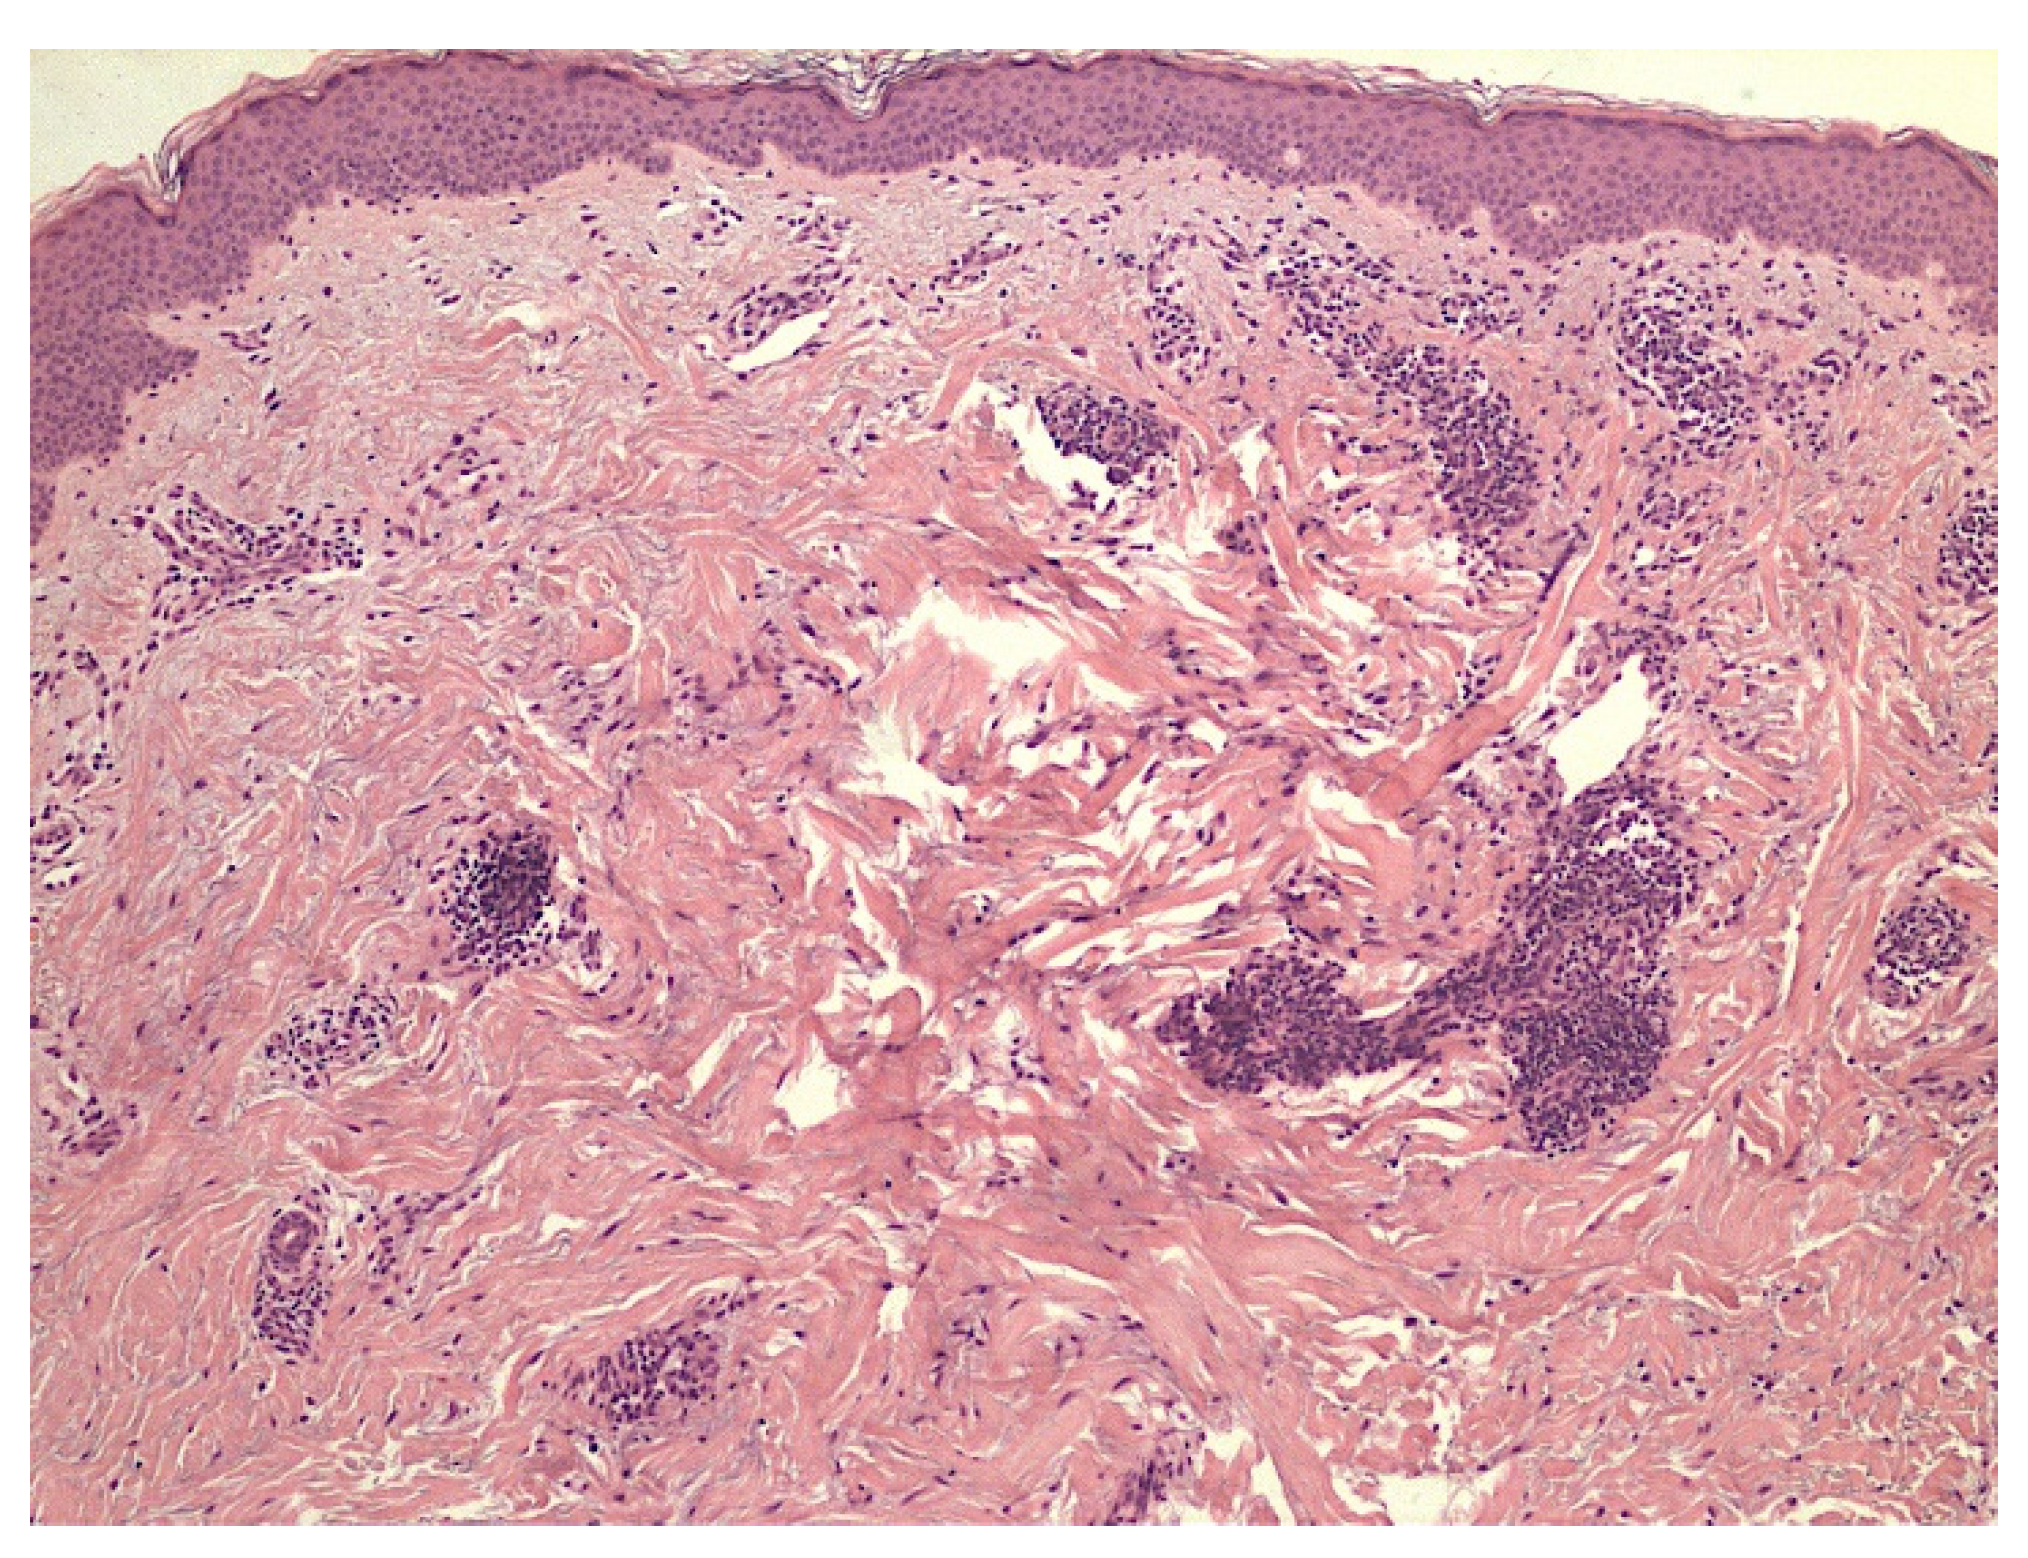

- Marušić, Z.; Korša, L.; Calonje, E. Dermal hyperneury. Clin. Dermatol. 2021, 39, 291–294. [Google Scholar] [CrossRef]

- Inaloz, H.S.; Kirtak, N.; Erguven, H.G.; Karakok, M.; Inaloz, S.S. Notalgia paresthetica with a significant increase in the number of intradermal nerves. J. Dermatol. 2002, 29, 739–743. [Google Scholar] [CrossRef]

- Ieremia, E.; Marušić, Z.; Mudaliar, V.; Kelly, S.; Rodriguez, P.G.; McNiff, J.M.; LeBoit, P.E.; Calonje, E. Expanding the clinical spectrum of dermal hyperneury: Report of nine new cases and a review of the literature. Histopathology 2019, 75, 738–745. [Google Scholar] [CrossRef] [PubMed]